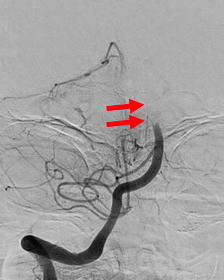

図2:矢印のように、脳底動脈の描出が見られません。 |

図3:右椎骨動脈撮影です。矢印のところで脳底動脈は閉塞しています。 |